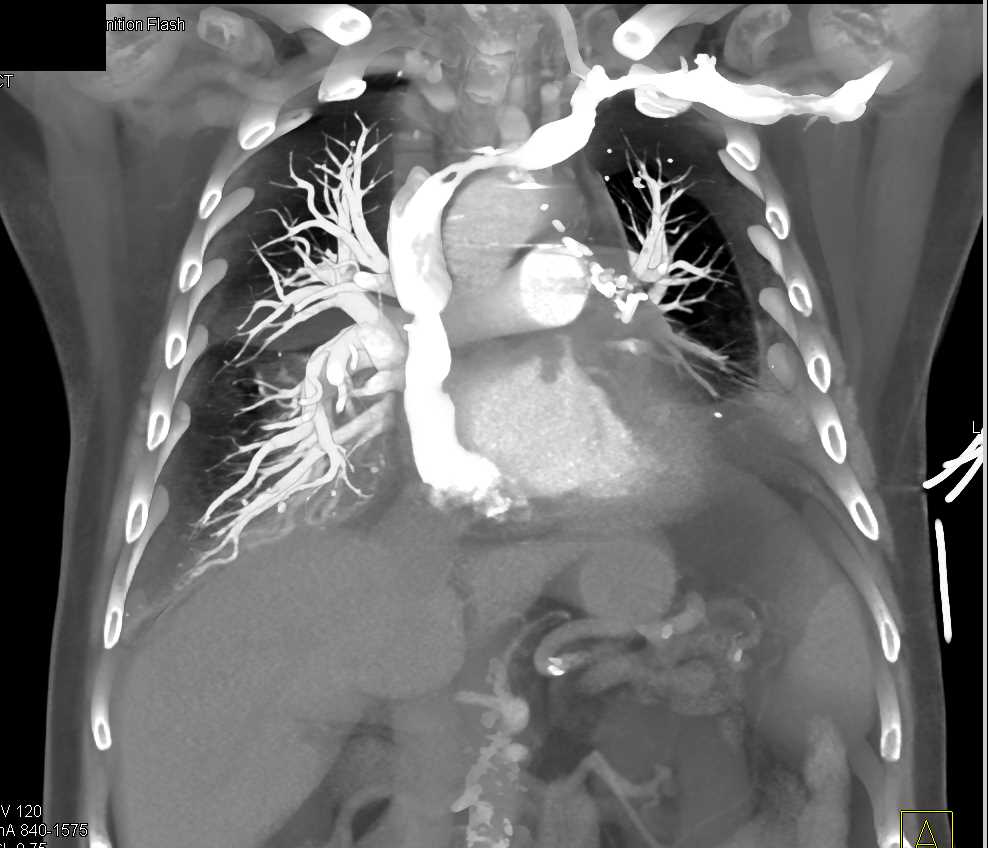

Post Cardiac Surgery Changes